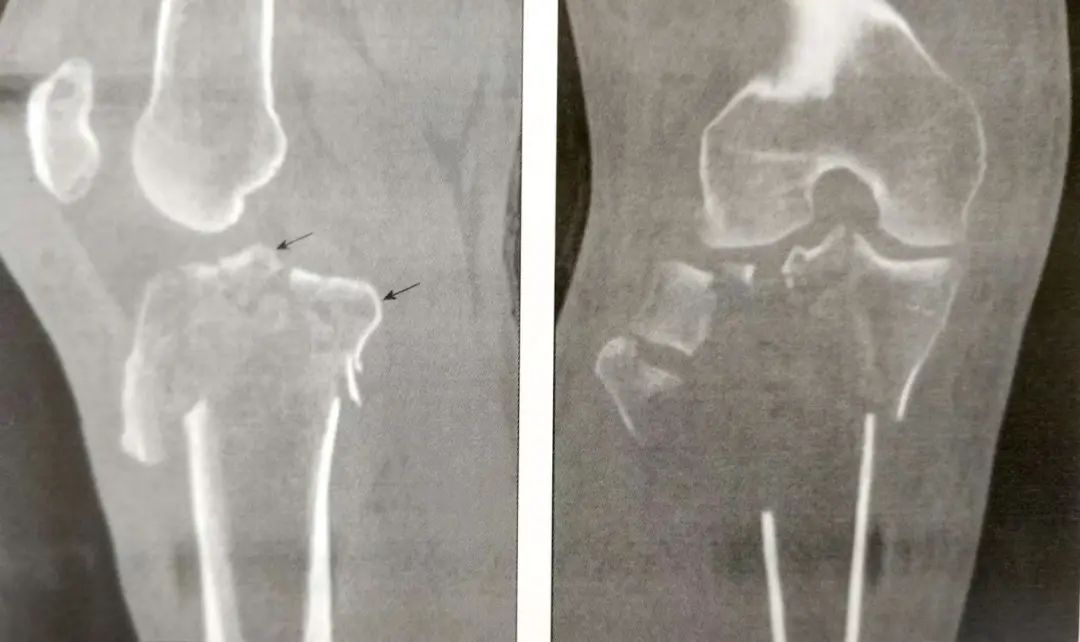

A:正位片;B:侧位片

A:前交叉韧带撕脱骨折(箭头)

B:后交叉韧带胫骨附着点撕脱骨折

▲前外侧髁间嵴骨折(箭头)